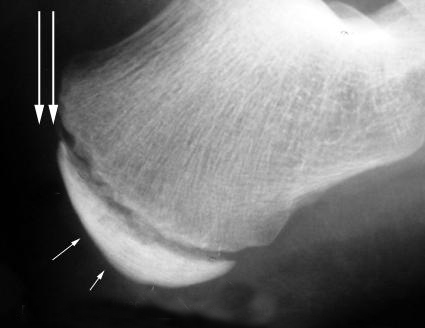

La Enfermedad de Sever o apófisis calcánea es una causa frecuente de dolor en el talón infantil. Suele aparecer entre los 7 y los 12 años de edad y es más frecuente en el género masculino y en aquellos niños que realizan actividad deportiva.

La apófisis calcánea es una inflamación aguda del cartílago por el desarrollo del talón. Durante el periodo de crecimiento se genera tensión muscular en el Tendón de Aquiles y la fascia del pie.